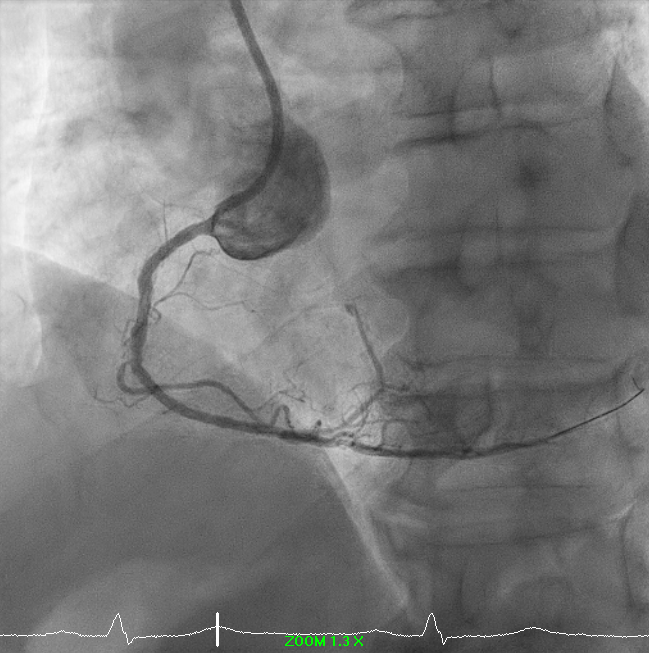

A drug-coated balloon strategy was employed: Prevail 2.5 ¡¿ 30 mm @ 8 ATM ¡¿ 60s and Selution SLR 3.0 ¡¿ 35 mm @ 6 ATM ¡¿ 60s. Final angiography showed TIMI 3 flow with no residual dissection. The case highlights a complex RCA ISR-CTO managed successfully with a contemporary DCB-based, stent-less strategy guided by IVUS and meticulous lesion preparation.

Right-dominant system. Proximal LAD shows 50% moderate calcified disease. Proximal LCx has 50% stenosis with severe calcification. RCA demonstrates severe diffuse proximal–mid 70% stenosis with moderate calcification and distal severe ISR-CTO with heavy calcification and minimal antegrade flow. Impression: Complex RCA ISR-CTO as culprit with moderate pLAD/pLCx disease.